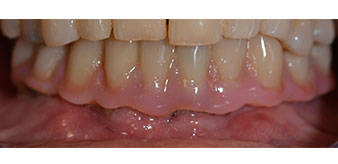

The impression and bite registration were then performed so that the dental technician could begin producing the provisional restoration immediately. This was then screwed in on the same day (Fig. 17 and 18).

Implants

Fig. 17

Fig. 18

Following the time required for the osseointegration, the final impression of the implants could be performed and the final denture produced accordingly (Fig. 19 and 20). At this point, the dentist and patient were able to decide together whether to use a ceramic or acrylic veneer and a zirconium or metal framework. In this case, Dr. Pascu’s team decided on an acrylic veneer based on the unclear prognosis for the maxillary dentition and the fact that tooth 24 is elongated. This type of veneer is generally considerably easier to adapt and can thus be subsequently altered to reflect the new situation in the maxilla.